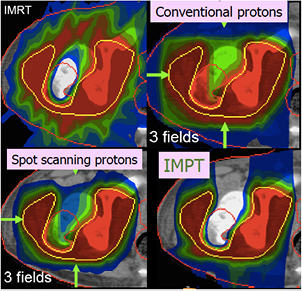

Radiotherapy is an essential component of cancer therapy. The combination of surgery, chemotherapy and radiotherapy is becoming a standard for most cancer patients. Out of the approximately 2/3 of cancer patients receiving radiotherapy, over 80% is irradiated with x-rays produced at linear electron accelerators (Linacs). The others receive specialized treatments such as gamma knife or brachytherapy. Only about 0.8% of the radiotherapy patients are treated with high-energy charged particles, but their number is rapidly increasing (figure 1). The rationale for using accelerated ions in therapy comes from the depth-dose distribution (figure 2), and was originally proposed by Wilson (1946), a student of Ernest Orlando Lawrence at the University of California in Berkeley (CA, USA). The advantages of the Bragg peak shown in figure 2 are quite obvious: unlike x-rays, the energy deposited per unit track increases with depth, therefore for a single beam the dose to the normal tissue will be much lower for ions than for photons when delivering the same dose to the tumor. While in x-ray therapy it is necessary to cross-fire the tumors from many different angles to increase the ratio of the doses to the tumor and normal tissues, only a few beams are necessary if charged particles are used (figure 3). Thus, the same radiation dose to the tumor (and therefore the same tumor control probability, TCP) can be achieved with lower integral dose to the normal tissue (lower normal tissue complication probability, NTCP); or the dose to the tumor can be increased (higher TCP) keeping the same NTCP as expected for x-rays. The most advanced x-ray delivery techniques, such as the intensity modulated radiotherapy (IMRT)5, are almost unbeatable in terms of target coverage, but the cost is an even higher 'dose bath' where the patient is immersed.

Both the longitudinal and lateral dose profiles (figure 4) resulting from the interaction of charged particles with the human tissues are important in CPT. The longitudinal profile is dominated by the inelastic electromagnetic interaction with atomic electrons, leading to a slow down of the primary particles. Lateral profile is mostly caused by the elastic scattering on target nuclei, and leads to a broadening of the beam. Nuclear interactions reduce the intensity of the primary beam and contribute to both longitudinal and lateral profiles.

Standard image High-resolution imageGenerally speaking, these processes (described in section 3) are fairly well understood, even if often not with the accuracy desirable for cancer therapy. The particle range, which is essential for irradiating the tumor, and not the surrounding organs at risk (OAR) in the Bragg peak region, can be calculated by the stopping power. As shown in figure 2(B), the narrow pristine Bragg peak must be extended to cover all the tumor area (spread-out-Bragg-peak, SOBP). This can be done either by passive modulation of the primary beam, or by changing the energy while raster scanning tumor slices with a pencil beam (figure 5). Scanning provides superior dose distributions compared to passive modulation, and greatly reduces the production of secondary neutrons, which may represent a risk for secondary cancers (see section 4.4). However, the interplay between pencil beam scanning and organ movement (figure 6) caused by breathing jeopardizes the dose distribution, and makes treatment of moving targets—e.g. lung tumors—with spot scanning much more complicated than with passive modulation (Bert and Durante 2011). The range uncertainty, due to organ movements and other causes (see section 5), requires to deliberately deliver a higher range as prescribed in order to avoid missing part of the tumor. This in turn can move the SOBP into an OAR, thus increasing toxicity. Lateral scattering broadens the beam and creates an undesired penumbra. Figure 7 shows that the penumbra is reduced by increasing the atomic mass of the ion used in therapy (see section 3.2). Nuclear interactions generate slow target fragments, which give a small contribution to the dose but can have high biological effectiveness. If particles heavier than protons are used, projectile fragmentation produces fast fragments with a mean velocity similar to the velocity of the primary ion. These fragments have lower mass and therefore higher range than the primary ions (see section 3.1), thus generating a longitudinal tail in the Bragg curve (figure 2). The angular distribution of the fragments is narrow in the forward direction, but the spread of the lighter fragments (protons and helium) contributes to the lateral widening of the beam.